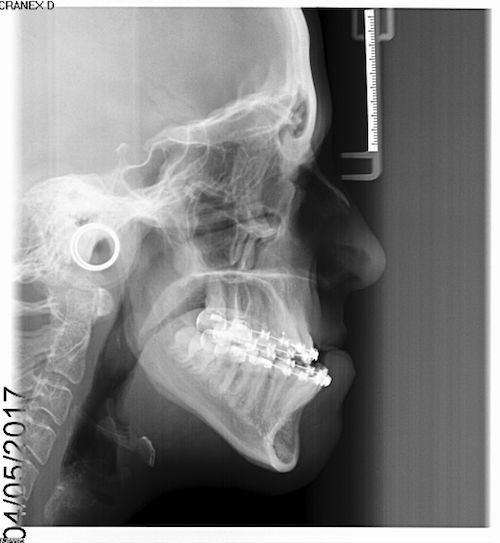

Surgery may involve either the upper jaw, lower jaw or both depending on the skeletal discrepancy of your particular case. This will allow the teeth to meet correctly and provide you with an improved bite, and often there is an accompanying improvement in your facial appearance and profile.

This will vary according to the type of surgery that has been planned by Mr Duncan’s team. All the incisions are carried out inside the mouth apart from 2 very small 2-3mm scars in both cheeks at the angle of your jaw (only if lower jaw surgery is carried out). Prescription bone cuts are then made and your jaws are moved into their planned position relative to each other. They are then secured in position with either titanium mini plates or screws, which stay in permanently unless they become loose or infected. The soft tissues are then sutures together with dissolving stitches, which do not need to be removed, and should dissolve themselves within 3 weeks.

You may need multiple extractions prior to surgery – orthodontic extractions are required to make space to align teeth, ready for the surgery. Lower wisdom teeth ideally need to be removed 6-9 months prior to any lower jaw surgery, as this makes your surgery more predictable, with a more favourable outcome.

No. The braces stay in position for the operation, and Mr Gowans will add on some metal hooks just before your surgery which are needed to position your jaws only DURING the operation. You may need a further 6-9 month course of orthodontics after the operation to ‘fine-tune’ your bite.